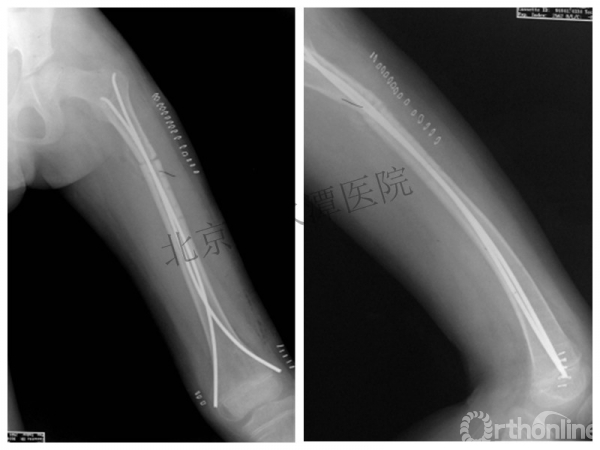

术后2年→再骨折→再次手术

钢板固定后一年

取板后再骨折→TEN

TEN取出后2个月

闭合复位再固定加尾帽